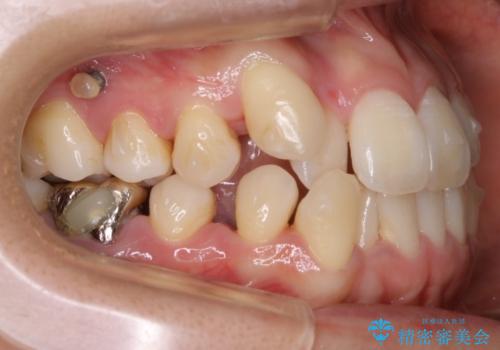

【非抜歯】インビザライン 隠れた前歯を並べる矯正治療

- 前歯のガタつき・奥に隠れてしまっている歯の矯正治療を希望されて初診来院されました。

遠心移動

非抜歯で矯正を行う場合にガタつきの改善に必要なスペースを作るために歯の遠心移動を行います。

最初の位置から奥に歯を移動させていくことで前歯のガタつきを改善したり、前歯の位置を後方に移動させることが可能となります。

その反面、歯の移動距離が大きくなるので治療期間が長くなる傾向があり、その分コントロールの難しさが上がることが予想されます。